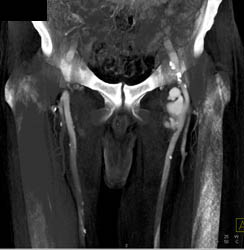

Diagnosis

Calcified Plaque Descending Aorta